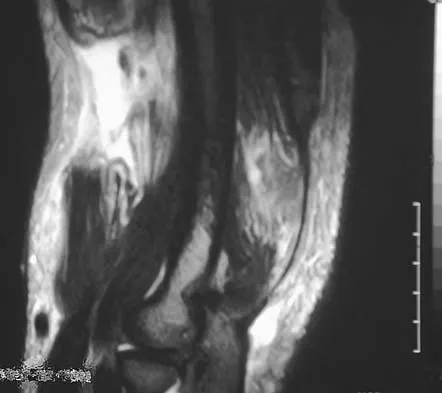

Figure 41 shows the MRI scan of a 38-year-old weightlifter. What does the arrow on the MRI scan indicate?

Explanation